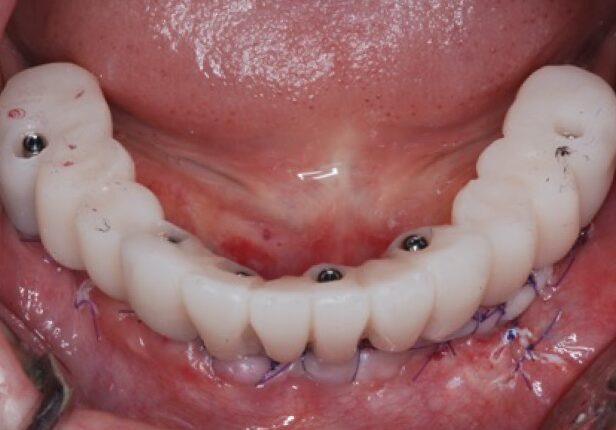

Coroa provisória logo após a colocação (1.ª: Capa)

Coroa provisória após 1 mês (2.ª)

Coroa provisória